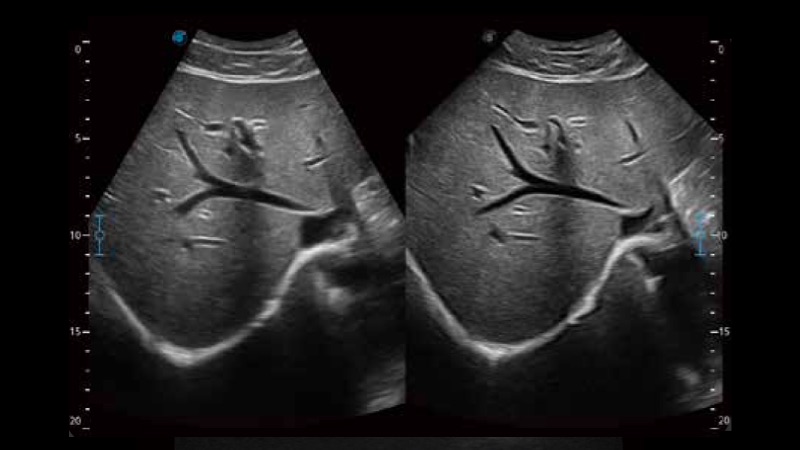

μ-Scan+新一代微米成像技术

新一代微米成像技术大大提高了器官和病变的可见性。高清对比度分辨率将抑制斑点噪声,同时保持真实的组织结构。

扩展成像技术

凸阵、线阵和相控阵探头进行实时扫描时,开启扩展成像模式,可以扩展超声图像视野,以便更完整地查看大的病灶或组织器官的解剖结构。

临床图像